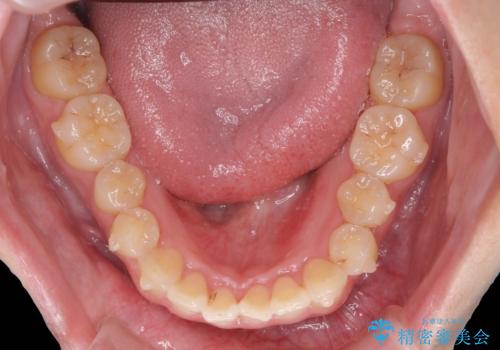

前歯のねじれをマウスピース矯正インビザラインで治療

- 長年気になっている、前歯のねじれの矯正治療を希望され来院されました。

十分にマウスピース矯正インビザラインで治療が可能と判断し、治療を進めることとしました。

長年気になっていた前歯のねじれが、ワイヤーをつけることなく矯正を行うことができ、大変喜んでいただくことができました。